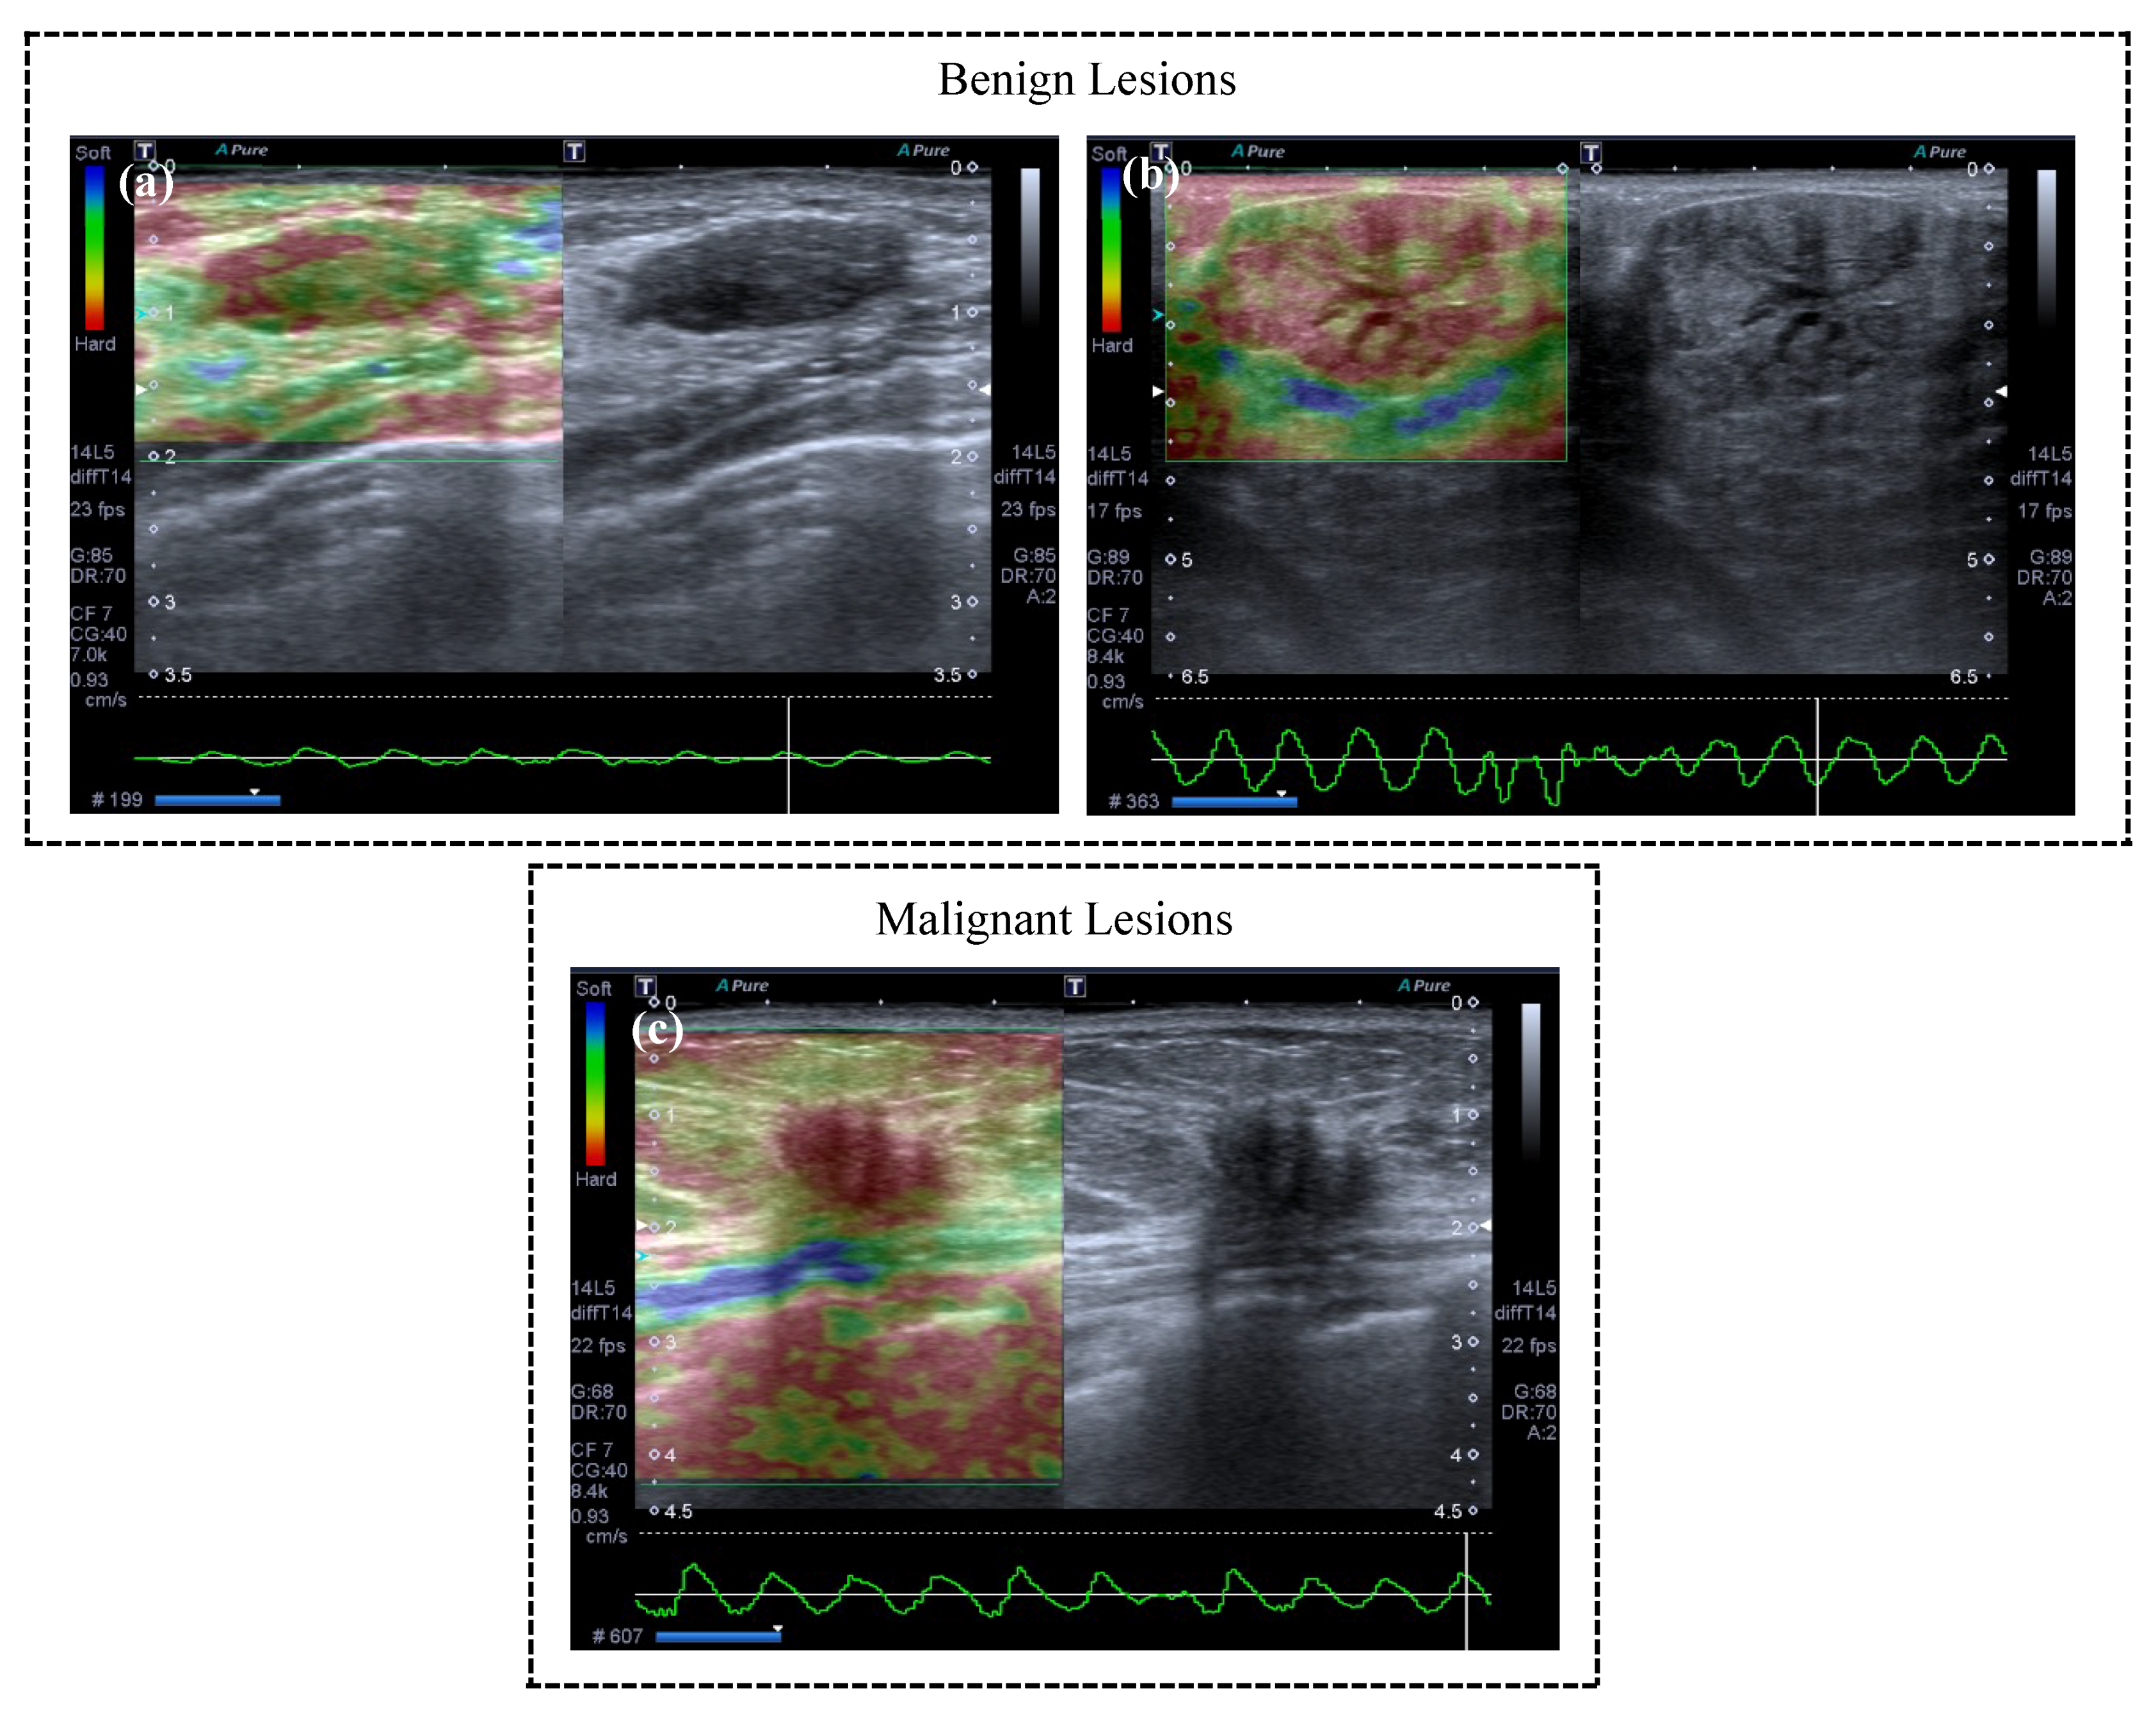

- Fleury, E.F.C.; Fleury, J.C.V.; Piato, S.; Junior, D.R. New elastographic classification of breast lesions during and after compression. Diagn. Interv. Radiol. 2009, 15, 96–103. [Google Scholar]